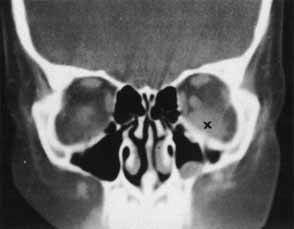

ORBITAL HEMORRHAGE

Hemorrhage can be localized to the subperiosteal potential space, extraconally, or intraconally within the orbital soft tissue, or within the belly of extraocular muscles. The condition can be associated with pain, nausea, diplopia, or decreased vision. The more obvious finding might be lid ecchymosis and edema but requires further examination for retroseptal signs. There may be conjunctival chemosis or expanding ecchymosis. Clinical findings reflect the mass effect of accumulating blood within the confines of the bony orbit and orbital septum (Fig. 2). Subperiosteal hematomas are usually restricted by the tight adherence of the periosteum to the orbital bone except in areas, such as suture sites, where this association is weakest. Hemorrhage localized to the muscle sheath may cause selective extraocular muscle restriction that requires radiologic studies to distinguish it from incarceration into a fracture site (Fig. 3). Localized bleeds within the orbital soft tissue can produce proptosis or dystopia. Diffuse hemorrhage may limit eye movement globally and increase retropulsive resistance. Increased intraorbital pressure on the globe and optic nerve may cause elevated intraocular pressure, choroidal folds, compressive retinal vascular compromise, or optic neuropathy, so maintaining vigilance for progressive, potential, vision-threatening situations is important.

Fig. 3 CT scan of inferior orbital hematoma (X) involving the inferior rectus muscle and causing severe upgaze and moderate downgaze limitation.